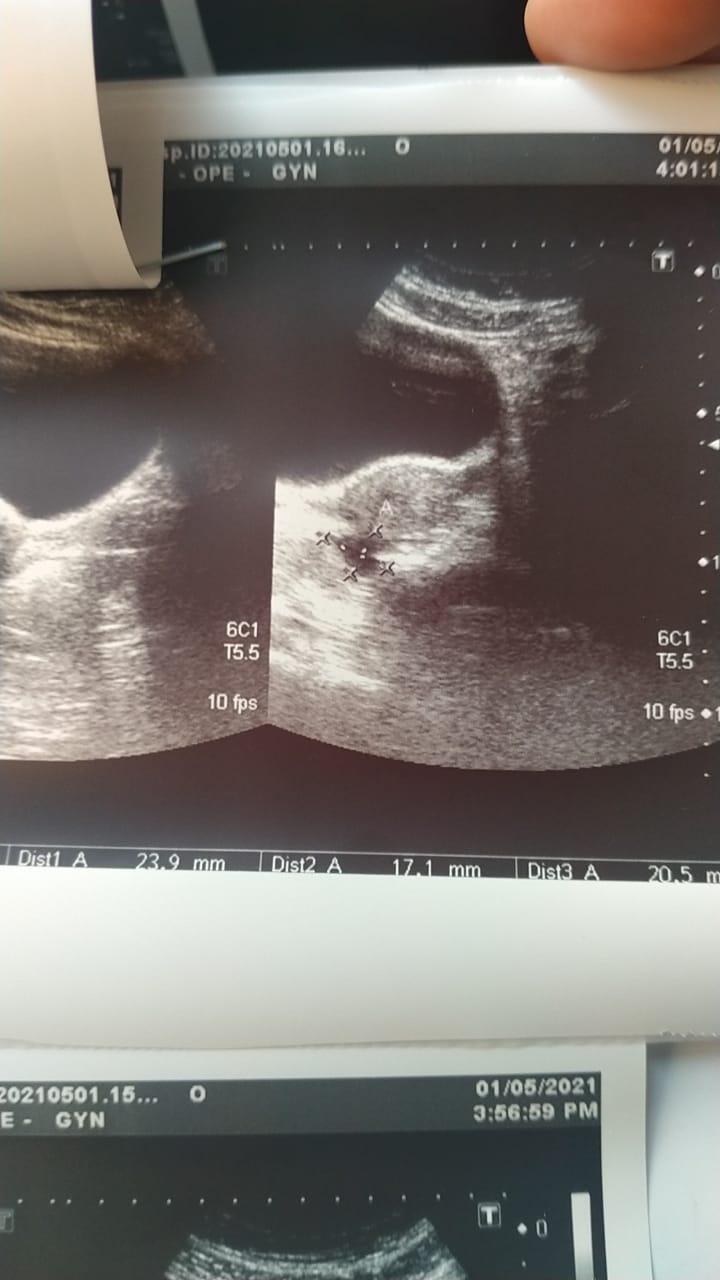

My ultrasound finding is::

A well defined elongated area measuring about 2.3 * 1.7 * 2cm (volume = 4.4ml) is seen in cul de Sac. It has internal septations.